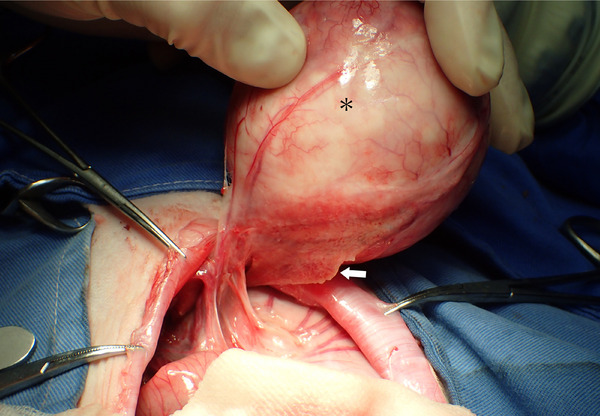

Results: Medical records were available for a total of 2128 rabbits, with 13 confirmed cases of intraabdominal abscess. Twelve cases considered eligible for this study were reviewed. Median age of the rabbits at onset was 18 months. Rabbits comprised 7 males (1 castrated) and 5 females (3 spayed), with 9 Lop-eared, 2 Netherland Dwarf and 1 Mini Rex. Common clinical signs were anorexia, decreased activity and abnormality of fecal production. Abdominal ultrasound and radiography revealed intraabdominal lesions in 12 and 7 cases, respectively. Exploratory laparotomy revealed intraabdominal abscess in all cases. Abscesses arose from the vermiform appendix in 6 cases and were associated with previous gastrointestinal perforation in 3 cases. The abscess was excised or incised with irrigation of the intraabscess cavity and administration of antibiotics. Nine cases showed an uneventful outcome (median survival time, 1044 days), including five cases showing growth of residual intraabdominal abscess.

Conclusions: Intraabdominal abscess in rabbits is commonly associated from the vermiform appendix and previous gastrointestinal perforation. Surgical intervention for intraabdominal abscess along with antibiotic therapy appears effective.